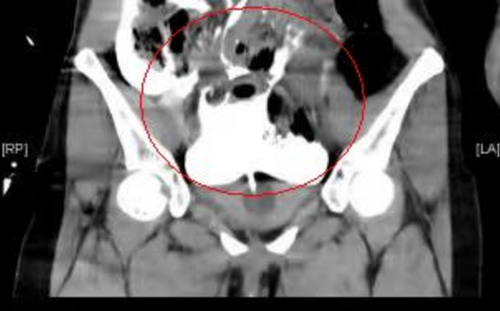

根据张迪的描述,医生先为张迪行了妇科相关检查及腹部CT平扫检查,但是CT除了发现少量盆腔积液外未找到其它问题,考虑到患者腹痛在加重,急诊科医生紧急请泌尿外科前来会诊。泌尿外科医生仔细追问其病史,结合CT检查,考虑存在膀胱损伤可能,立即留置导尿管,见有少量淡红色血尿。最后经过膀胱造影CT检查,张迪确诊为腹膜内型膀胱破裂,腹腔内已有大量尿液,所以才引起腹膜炎刺激性腹痛等症状。

CT显示腹腔盆腔内大量积液(尿液),膀胱造影尿液混杂着造影剂,在盆腔、腹腔都显影出白色